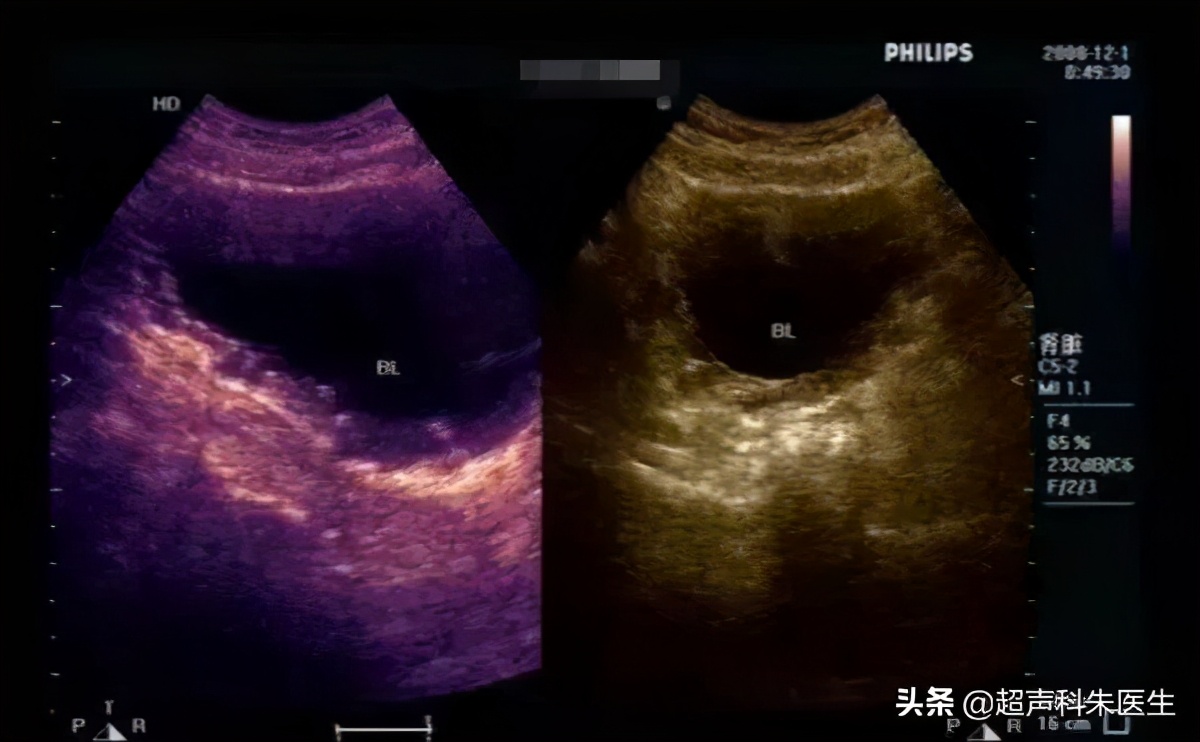

三、弥漫增厚型:声像图表现为膀胱壁呈节段性或弥漫性增生肥厚,轻者膀胱壁增厚仅数毫米,重者整个膀胱壁增厚可达几厘米,膀胱腔明显缩小,粘膜粗糙不光滑,回声不均,可有散在分布的细小蜂窝状小囊性暗区,粘膜下层结构层次可辨认,膀胱顺应性减低。本型可导致双肾盂积水,肾功能衰竭。CDFI及CDE 可见丰富的血流信号, 多为细线状平行于膀胱壁的静脉血流,也可偶见动脉血流,多为低速高阻型。